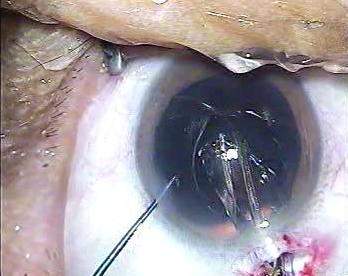

白内障超声乳化+折叠型人工晶体植入术,仍然是“Divide and Conquer”手法。但是术中助手配合不满意,手术节奏不紧凑。